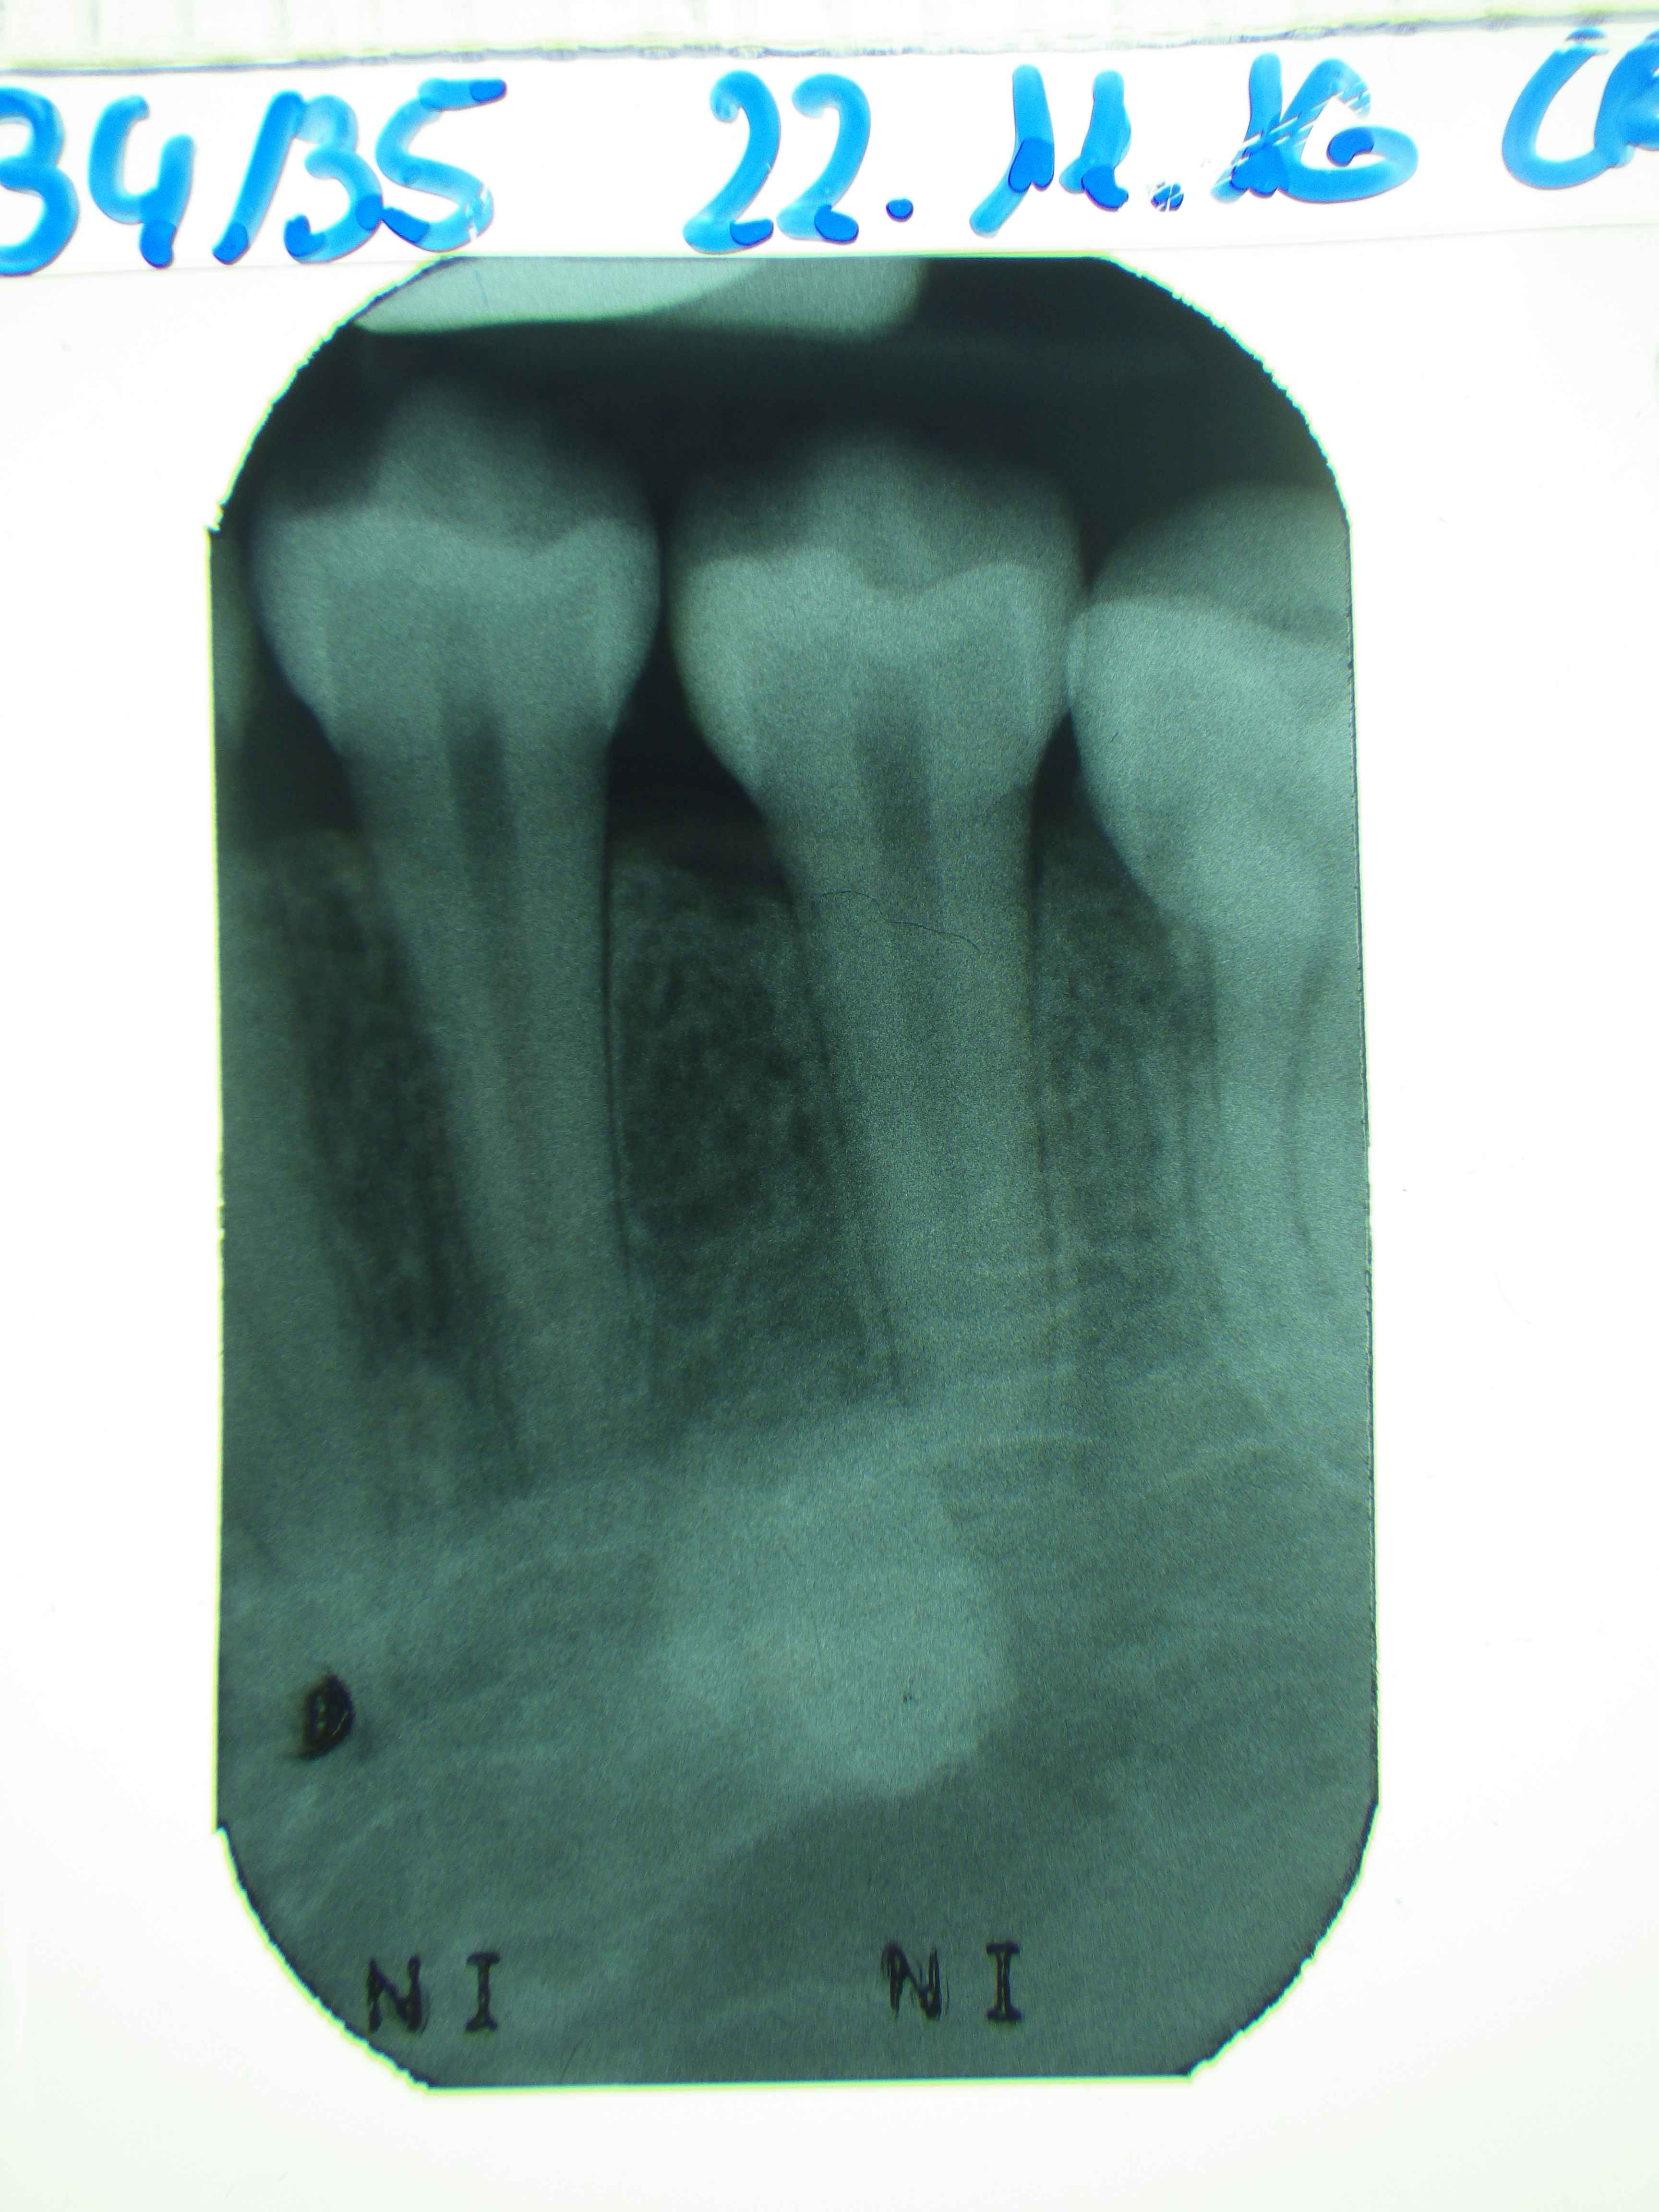

f-34-35-zahnroentgenfilm Veröffentlicht 6. Januar 2017 am 3456 × 4608 in Neupatientin mit Sammlung seltener Befunde